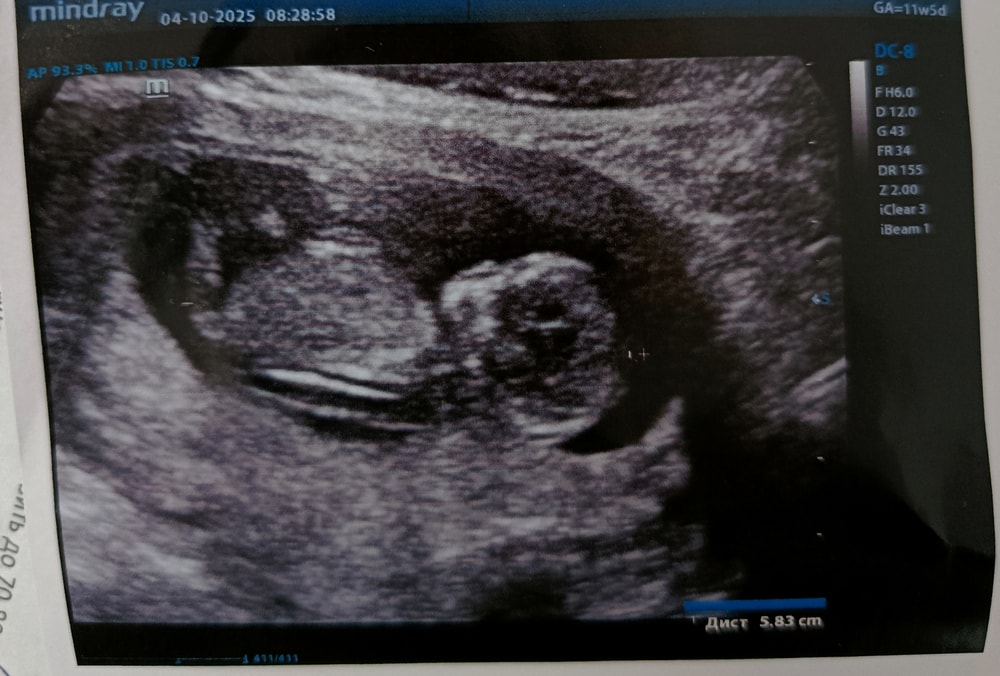

Прошла первый скрининг.

Пол малышаДевочки посмотрите пожалуйста может виден пол, УЗИст соответственно не сказала и даже не предположила.

Похожа на девочку ?

Жанет , по вашим фоткам можно нагадывать девочку. Но такое качество, что лучше не начинать гадать))

На 12 неделе беременности половые органы эмбриона не имеют различий, позволяющих определить пол- даже при непосредственном осмотре. Поэтому грамотный врач никогда пол на таком сроке ни определять, ни предполагать не будет, а интересующейся женщине объяснит, что это невозможно.